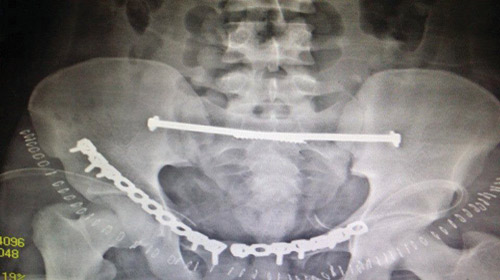

وبعد استقرار الحالة العامة للمريض، تمت مناظرة الكسور الموجودة من قِبل استشاري ورئيس قسم العظام، والذي قرَّر بإجراء تدخل جراحي لفتح وتثبيت الكسور المتعددة بالحوض بواسطة شرائح ومسامير معينة، وبالفعل تم عمل التحاليل اللازمة، ودخول المريض لغرفة العمليات، حيث تم فتح وتثبيت الكسور. وبحمد الله وتوفيقه تمت العمليات جميعها بالحوض في جلسة واحدة وبنجاح تام ومكث المريض بالمستشفى لعدة أيام بعد الجراحة للاطمئنان على الحالة العامة والغيار المستمر على الجروح. وبحمد الله خرج المريض من المستشفى بحالة جيدة واستمر في المتابعة بالعيادة الخارجية بقسم العظام بالمستشفى حتى تمكَّن من المشي بصورة منتظمة وطبيعية.